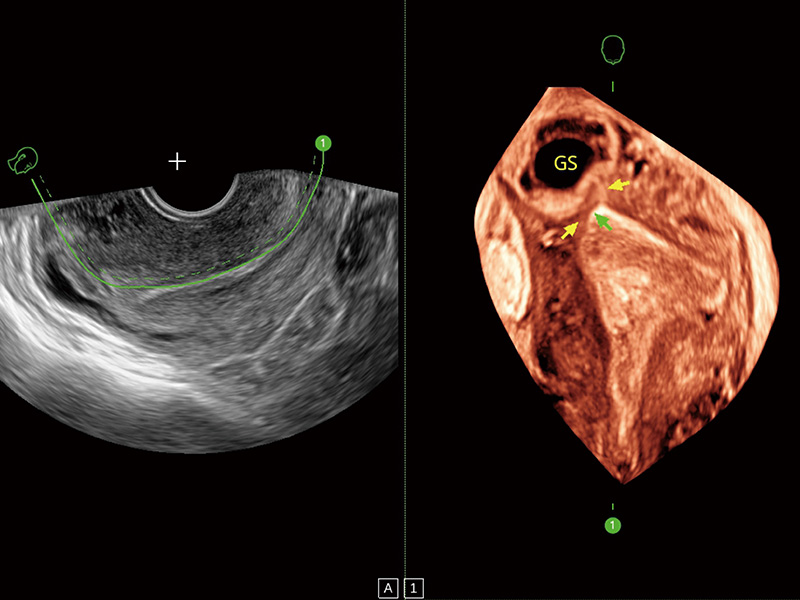

临床图

中央型宫腔粘连

单角子宫

腔内三维成像技术获得显著提升,超大扇角在满足日常基础扫查的同时,支持卵泡自动测量及多种三维渲染模式,为您提供更多的诊断信息,尤其是在子宫畸形的诊断,内膜及肿瘤占位观测中起到了重要的作用。